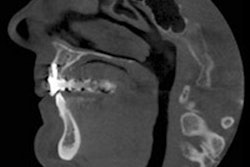

Dental x-rays are a known human carcinogen and a common source of radiation exposure, with no level considered completely safe, the authors noted. Therefore, dental radiographs should be limited to times when clinical benefits outweigh the risks and their use detached from dentists' compensation or how patients pay for services, they wrote. Nonetheless, some studies have found relationships between dental imaging and meningiomas, salivary gland tumors, and thyroid tumors.